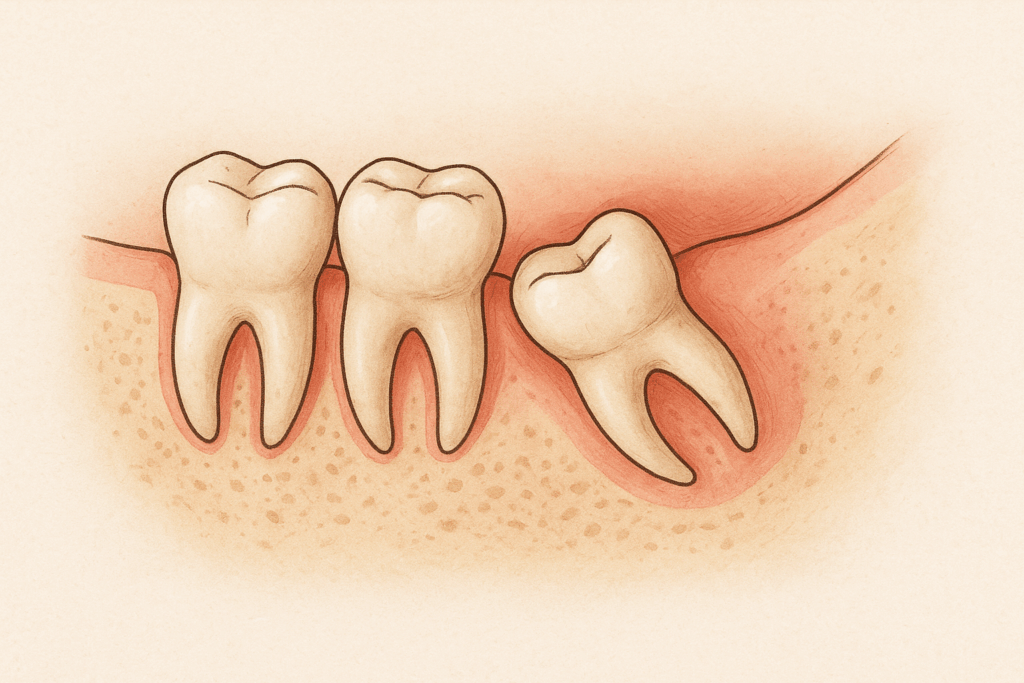

Our team is great at removing tricky teeth like wisdom teeth, using gentle methods that help you feel better faster.